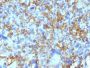

This MAb reacts with a 28 kDa chain of HLA-DRB1 antigen, a member of MHC class II molecules. It does not cross react with HLA-DP and HLA-DQ. The L243 antibody recognizes a different epitope than the LN3 monoclonal antibody, and these antibodies do not cross-block binding to each other's respective epitopes. HLA-DR is a heterodimeric cell surface glycoprotein comprised of a 36 kDa alpha (heavy) chain and a 28 kDa beta (light) chain. It is expressed on B-cells, activated T-cells, monocytes/macrophages, dendritic cells and other non-professional APCs. In conjunction with the CD3/TCR complex and CD4 molecules, HLA-DR is critical for efficient peptide presentation to CD4 T cells. It is an excellent histiocytic marker in paraffin sections producing intense staining. True histiocytic neoplasms are similarly positive. HLA-DR antigens also occur on a variety of epithelial cells and their corresponding neoplastic counterparts. Loss of HLA-DR expression is related to tumor microenvironment and predicts adverse outcome in diffuse large B-cell lymphoma.Primary antibodies are available purified, or with a selection of fluorescent CF® Dyes and other labels. CF® Dyes offer exceptional brightness and photostability. Note: Conjugates of blue fluorescent dyes like CF®405S and CF®405M are not recommended for detecting low abundance targets, because blue dyes have lower fluorescence and can give higher non-specific background than other dye colors.

Positive Control

Higher concentration may be required for direct detection using primary antibody conjugates than for indirect detection with secondary antibody|Immunofluorescence: 0.5-1 ug/mL|Immunohistology formalin-fixed 0.25-0.5 ug/mL|Staining of formalin-fixed tissues is enhanced by boiling tissue sections in 10 mM citrate buffer, pH 6.0, for 10-20 min followed by cooling at RT for 20 minutes|Flow Cytometry 0.5-1 ug/million cells/0.1 mL|Western blotting 0.5-1 ug/mL|Does not react with mouse; others not known|Optimal dilution for a specific application should be determined by user